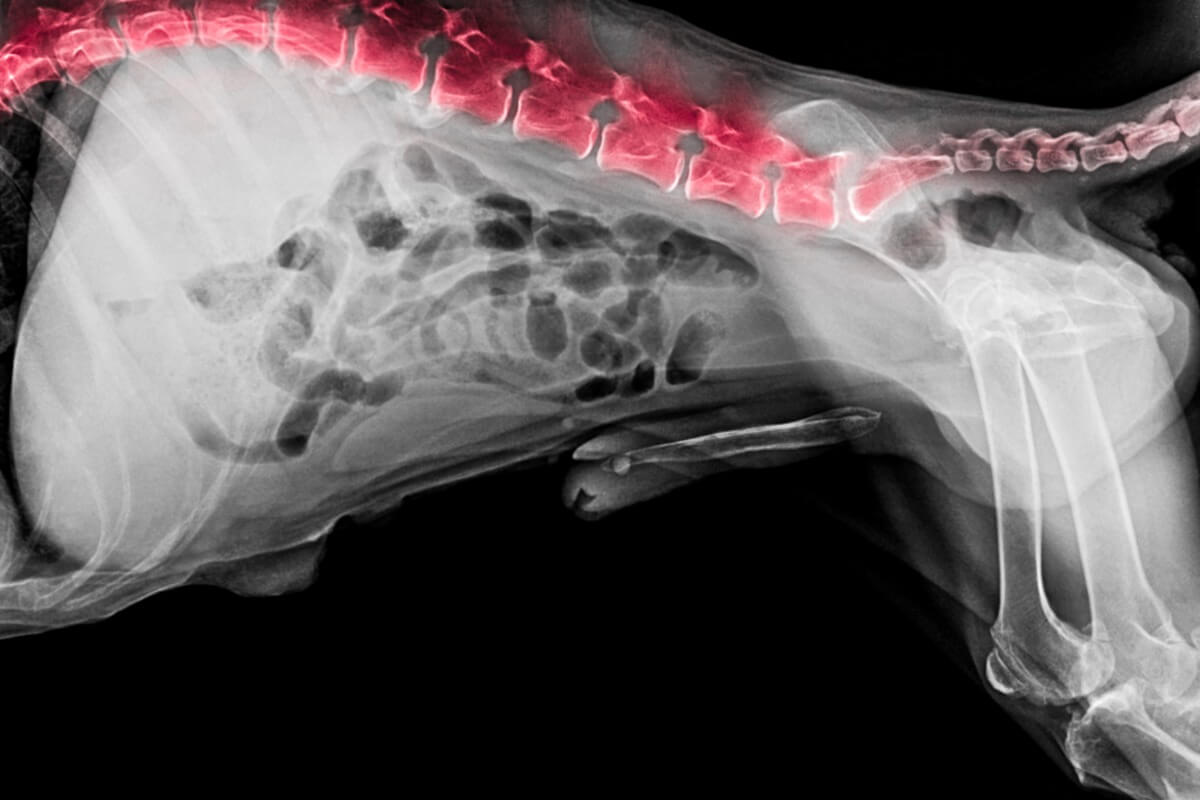

På klinikken utføres en rekke grunnleggende tester for å fastslå årsaken til skaden. Den vanligste er en røntgen, som differensialdiagnosen verifiseres mot andre årsaker som kan gi lignende symptomer, for eksempel svulster eller brudd. Det kan også være nødvendig å ta en CT-skanning eller MR.